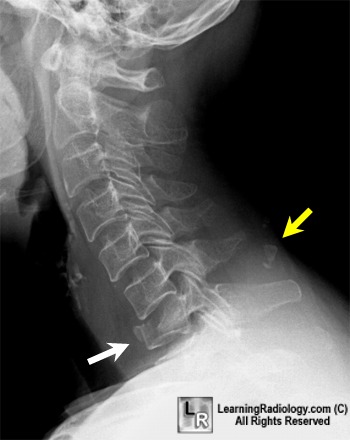

Flexion Teardrop Fracture

A lateral radiograph of the cervical spine demonstrates a compression fracture of C7 with a triangle-like fracture anteriorly (white arrow), not to be confused with the more benign extension teardrop fracture. There is loss of stature of C7 and widening of the interspinous distance between C6 and C7 (yellow arrow) from disruption of the posterior ligaments. There is also a fracture of the spinous process of C6. These fractures are caused by severe flexion and compression and frequently produce neurologic impairment.